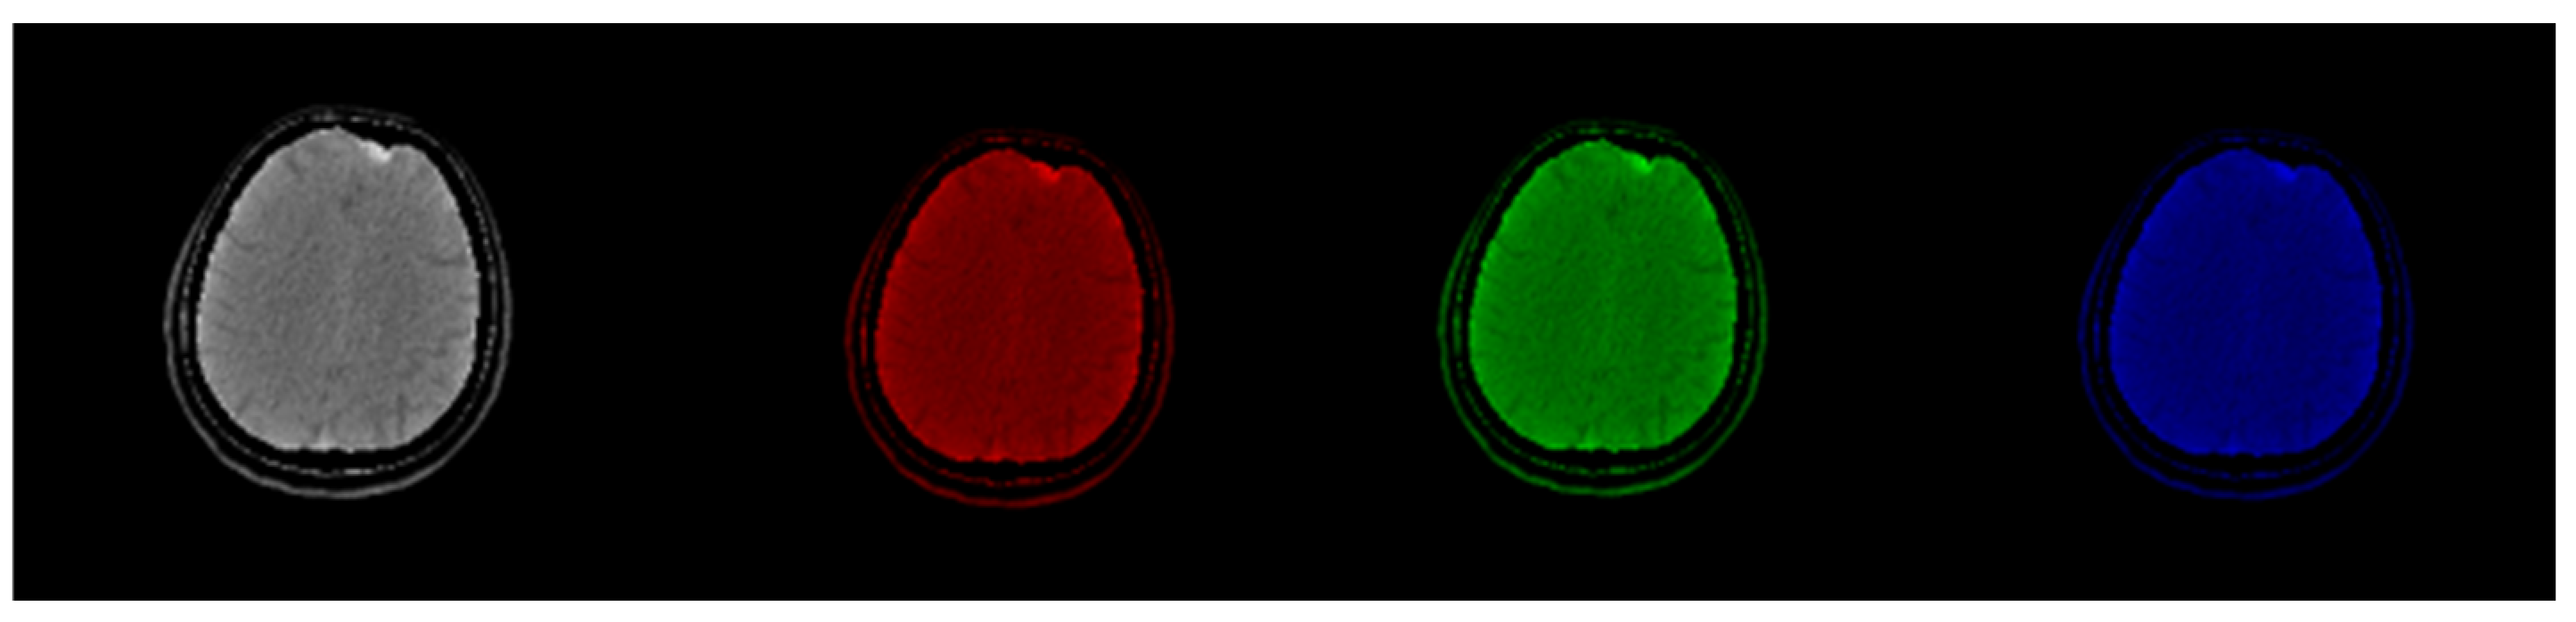

Figure 8 shows raw, windowed, and CIT-transformed CT and PET slices including their associated color channels. Interestingly, useful information is present in different channels for the two modalities.

Figure 8.

CIT of brain CT (left block) and corresponding PET (right block). 1. Normalized image of 16-bit integer to 8-bit grayscale 2. Image transformed data by applying window thresholding normalized to grayscale 3. CIT on RGB channels giving priority for the most significant byte to Red Channel, then Green, then Blue using equal distribution of R,G,B levels. 4. Red channel of Image 3. 5. Green channel of Image 3. 6. Blue channel of Image 3.